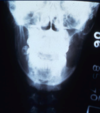

What is this radiographical finding?

Metastatic Carcinoma to Jaw Bones

C. Periapical image of a metastatic lesion of breast carcinoma; note the irregular widening of the periodontal membrane spaces and patchy sclerotic bone reaction, especially around the roots of the molars